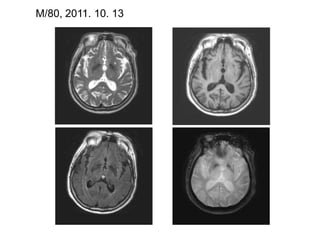

M/80, 2011. 10. 13

2. LacunesMRI definition(ref. 2): small hyperintense lesions on T2WI (ref. 2): corresponding distinctive low intensity area on T1WI: Maximum size of lacune (ref. 4)  - with a diameter of 5-10 mm: On CT (ref. 4)  - areas of more or less complete focal tissue destruction  - clearly defined borders with marked central hypodensity on CT: On MRI (ref. 4)  - low intensity on T1WI, proton-density and FLAIR scans  - high intensity on T2WI    -> isointense to CSF

2. LacunesMRI definition(ref.2): small hyperintense lesions on T2WI (ref. 2): corresponding distinctive low intensity area on T1WI: Maximum size of lacune (ref. 4) - with a diameter of 5-10 mm: On CT (ref. 4) - areas of more or less complete focal tissue destruction - clearly defined borders with marked central hypodensity on CT: On MRI (ref. 4) - low intensity on T1WI, proton-density and FLAIR scans - high intensity on T2WI -> isointense to CSF